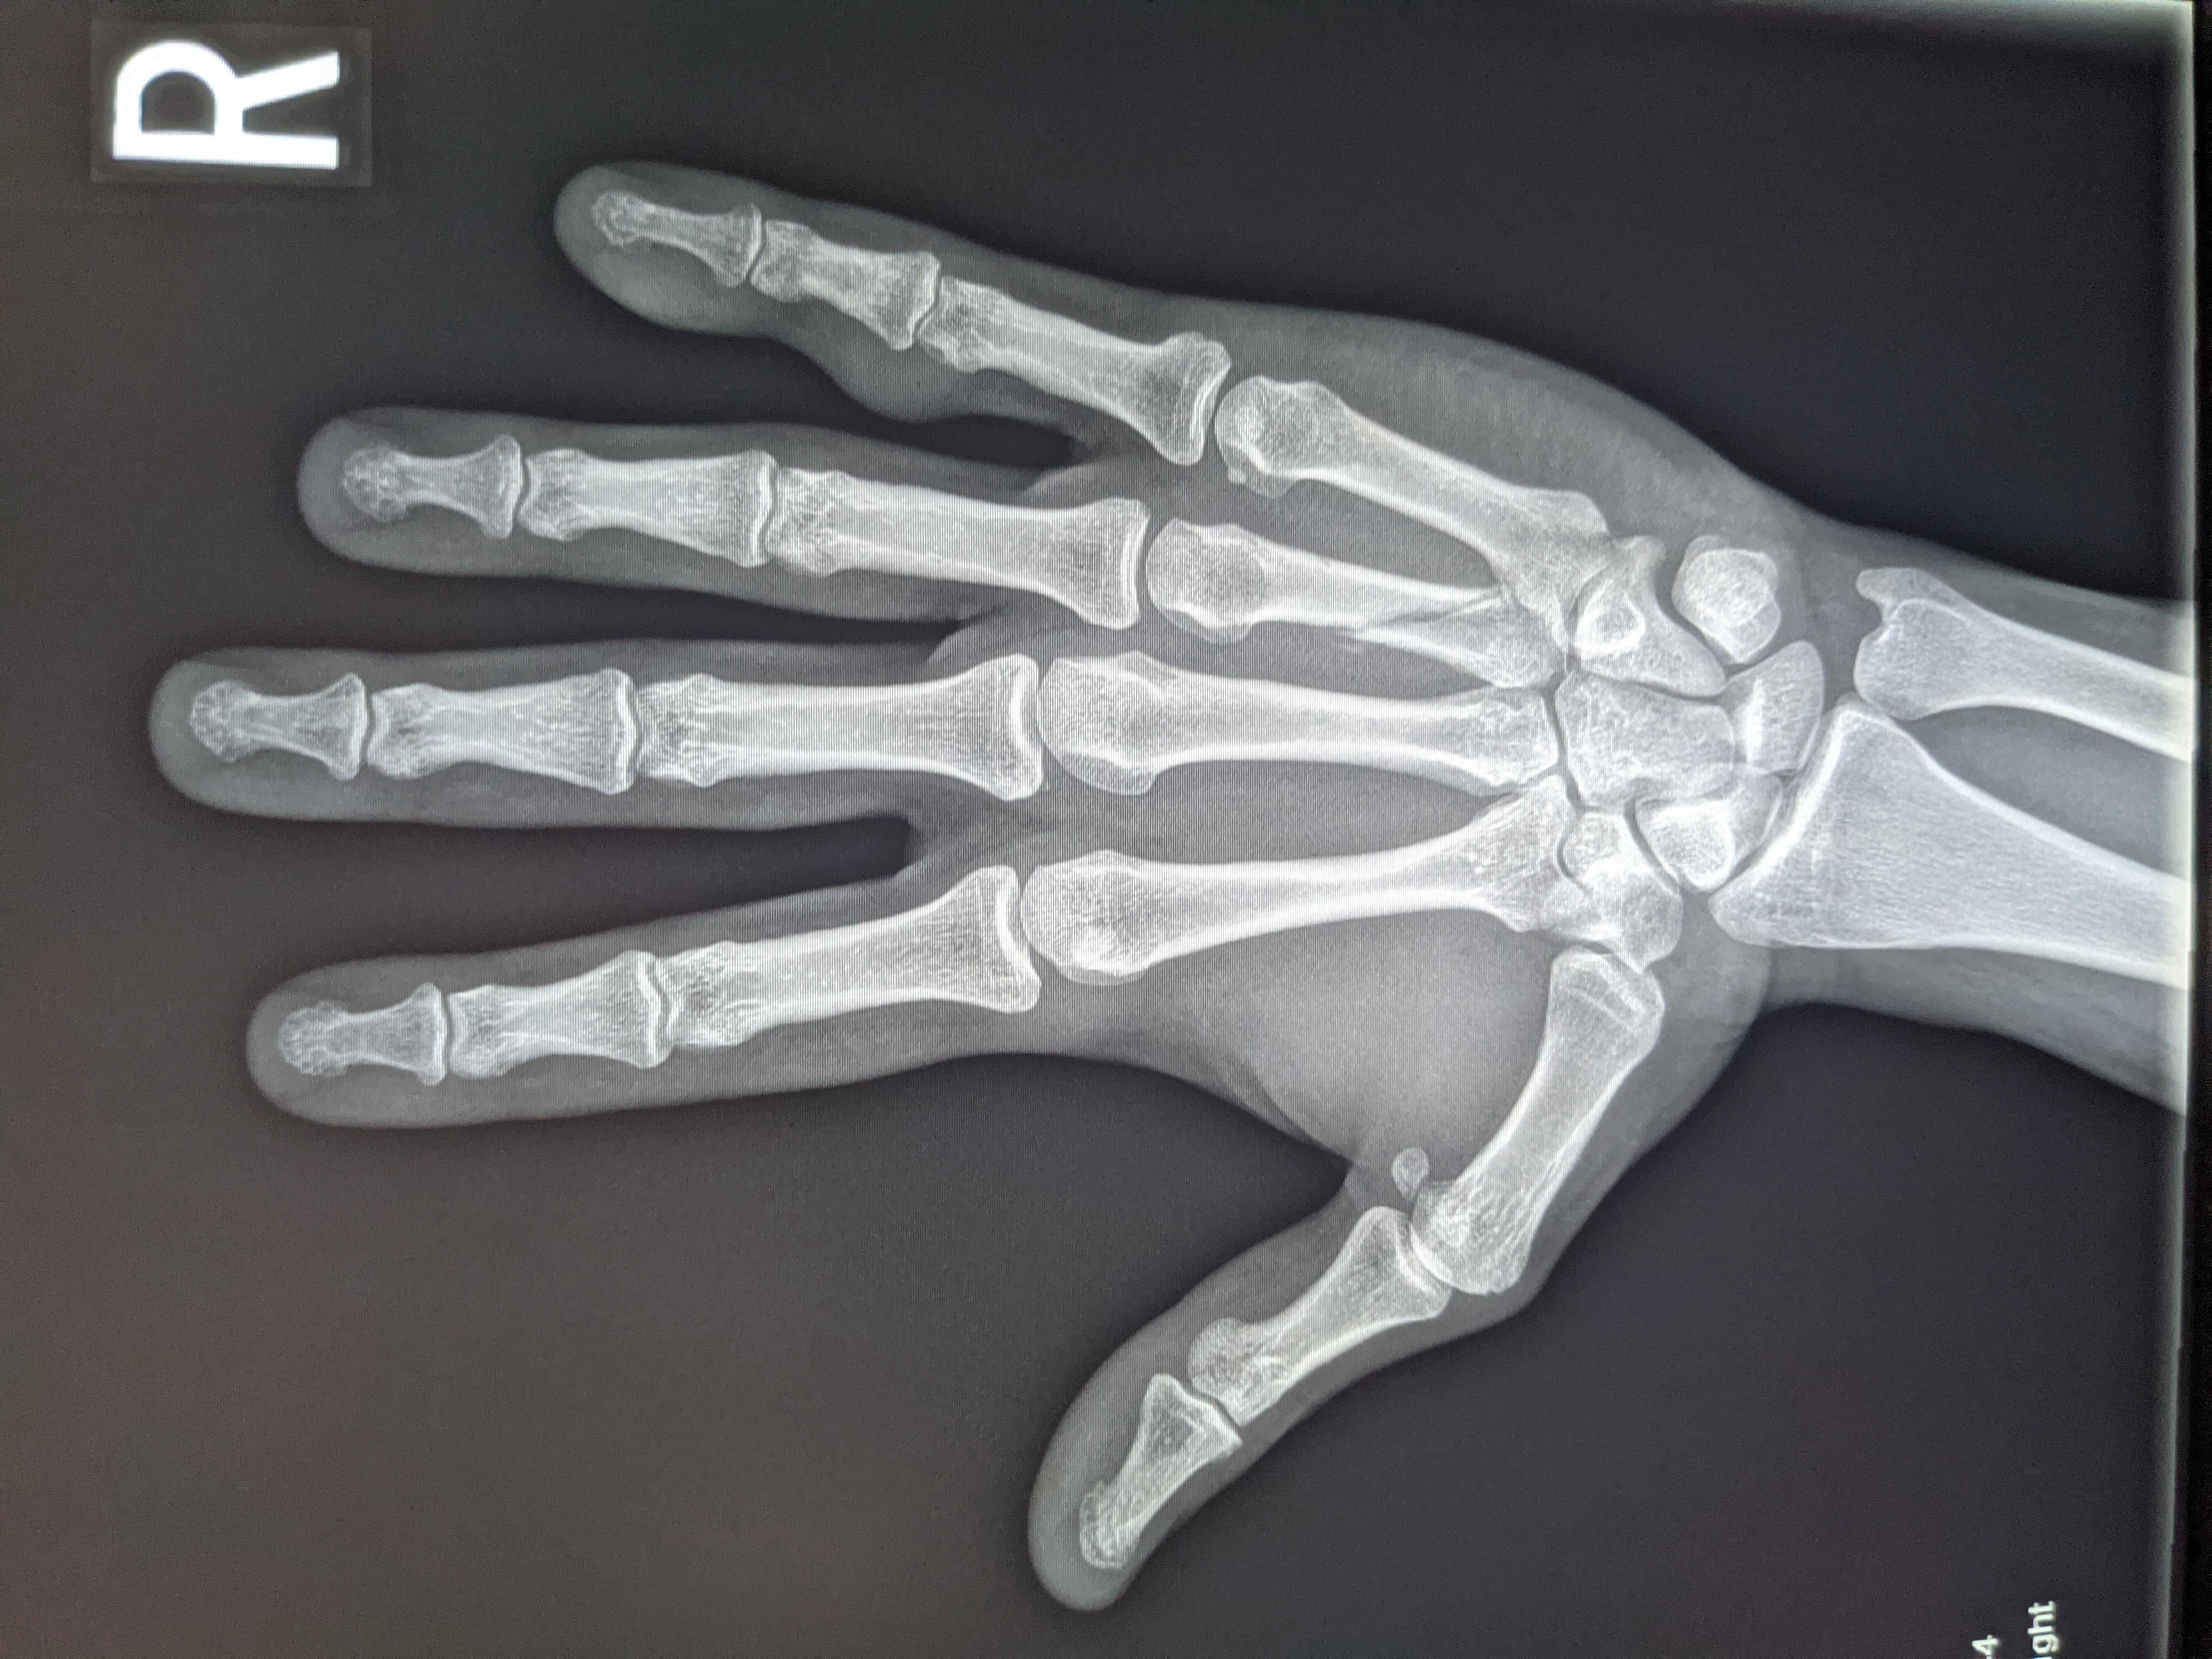

Which immediately requested an X-ray, and you really don’t have to be a doctor to figure this out, just by looking at the image below you can see a broken finger.